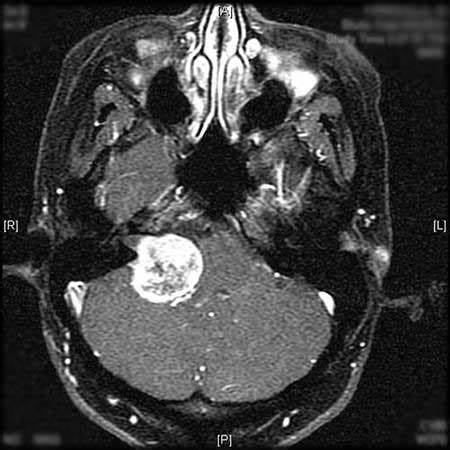

听神经瘤属于良性肿瘤(非恶性也非癌),通常生长缓慢,平均年增长率为2mm,听神经瘤的发病率每年约为1/10万人,早期诊断常有困难。 听神经瘤常被认为是脑肿瘤,但其实并不位于...

听神经瘤 ,更准确地说是前庭神经鞘瘤,是一种生长在平衡和听力神经上的良性肿瘤。这些神经缠绕在一起形成前庭耳蜗神经,从内耳到大脑。由听神经瘤引起的听力损失通常只发生在...

听神经瘤 多数发生于听神经的前庭神经,随着肿瘤生长变大,压迫桥脑外侧面和小脑前缘,充满于小脑桥脑角内。听神经瘤占颅内肿瘤的8.43%。好发于中年人,高峰在30-50岁。病程相对...